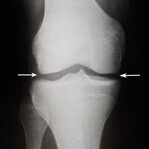

Choroba zwyrodnieniowa stawów stopniowo niszczy tkankę chrzęstną i prowadzi do deformacji stawów. Z czasem nawet najprostsze ruchy stają się niemożliwe, a ból staje się stały. Odpowiednia terapia pomaga zatrzymać postęp choroby.

Obrzęk i stan zapalny stawu kolanowego są sygnałem ostrzegawczym poważnych zaburzeń. Bez leczenia może to prowadzić do całkowitej utraty sprawności ruchowej i konieczności interwencji chirurgicznej. Reaguj natychmiast na pierwsze objawy!